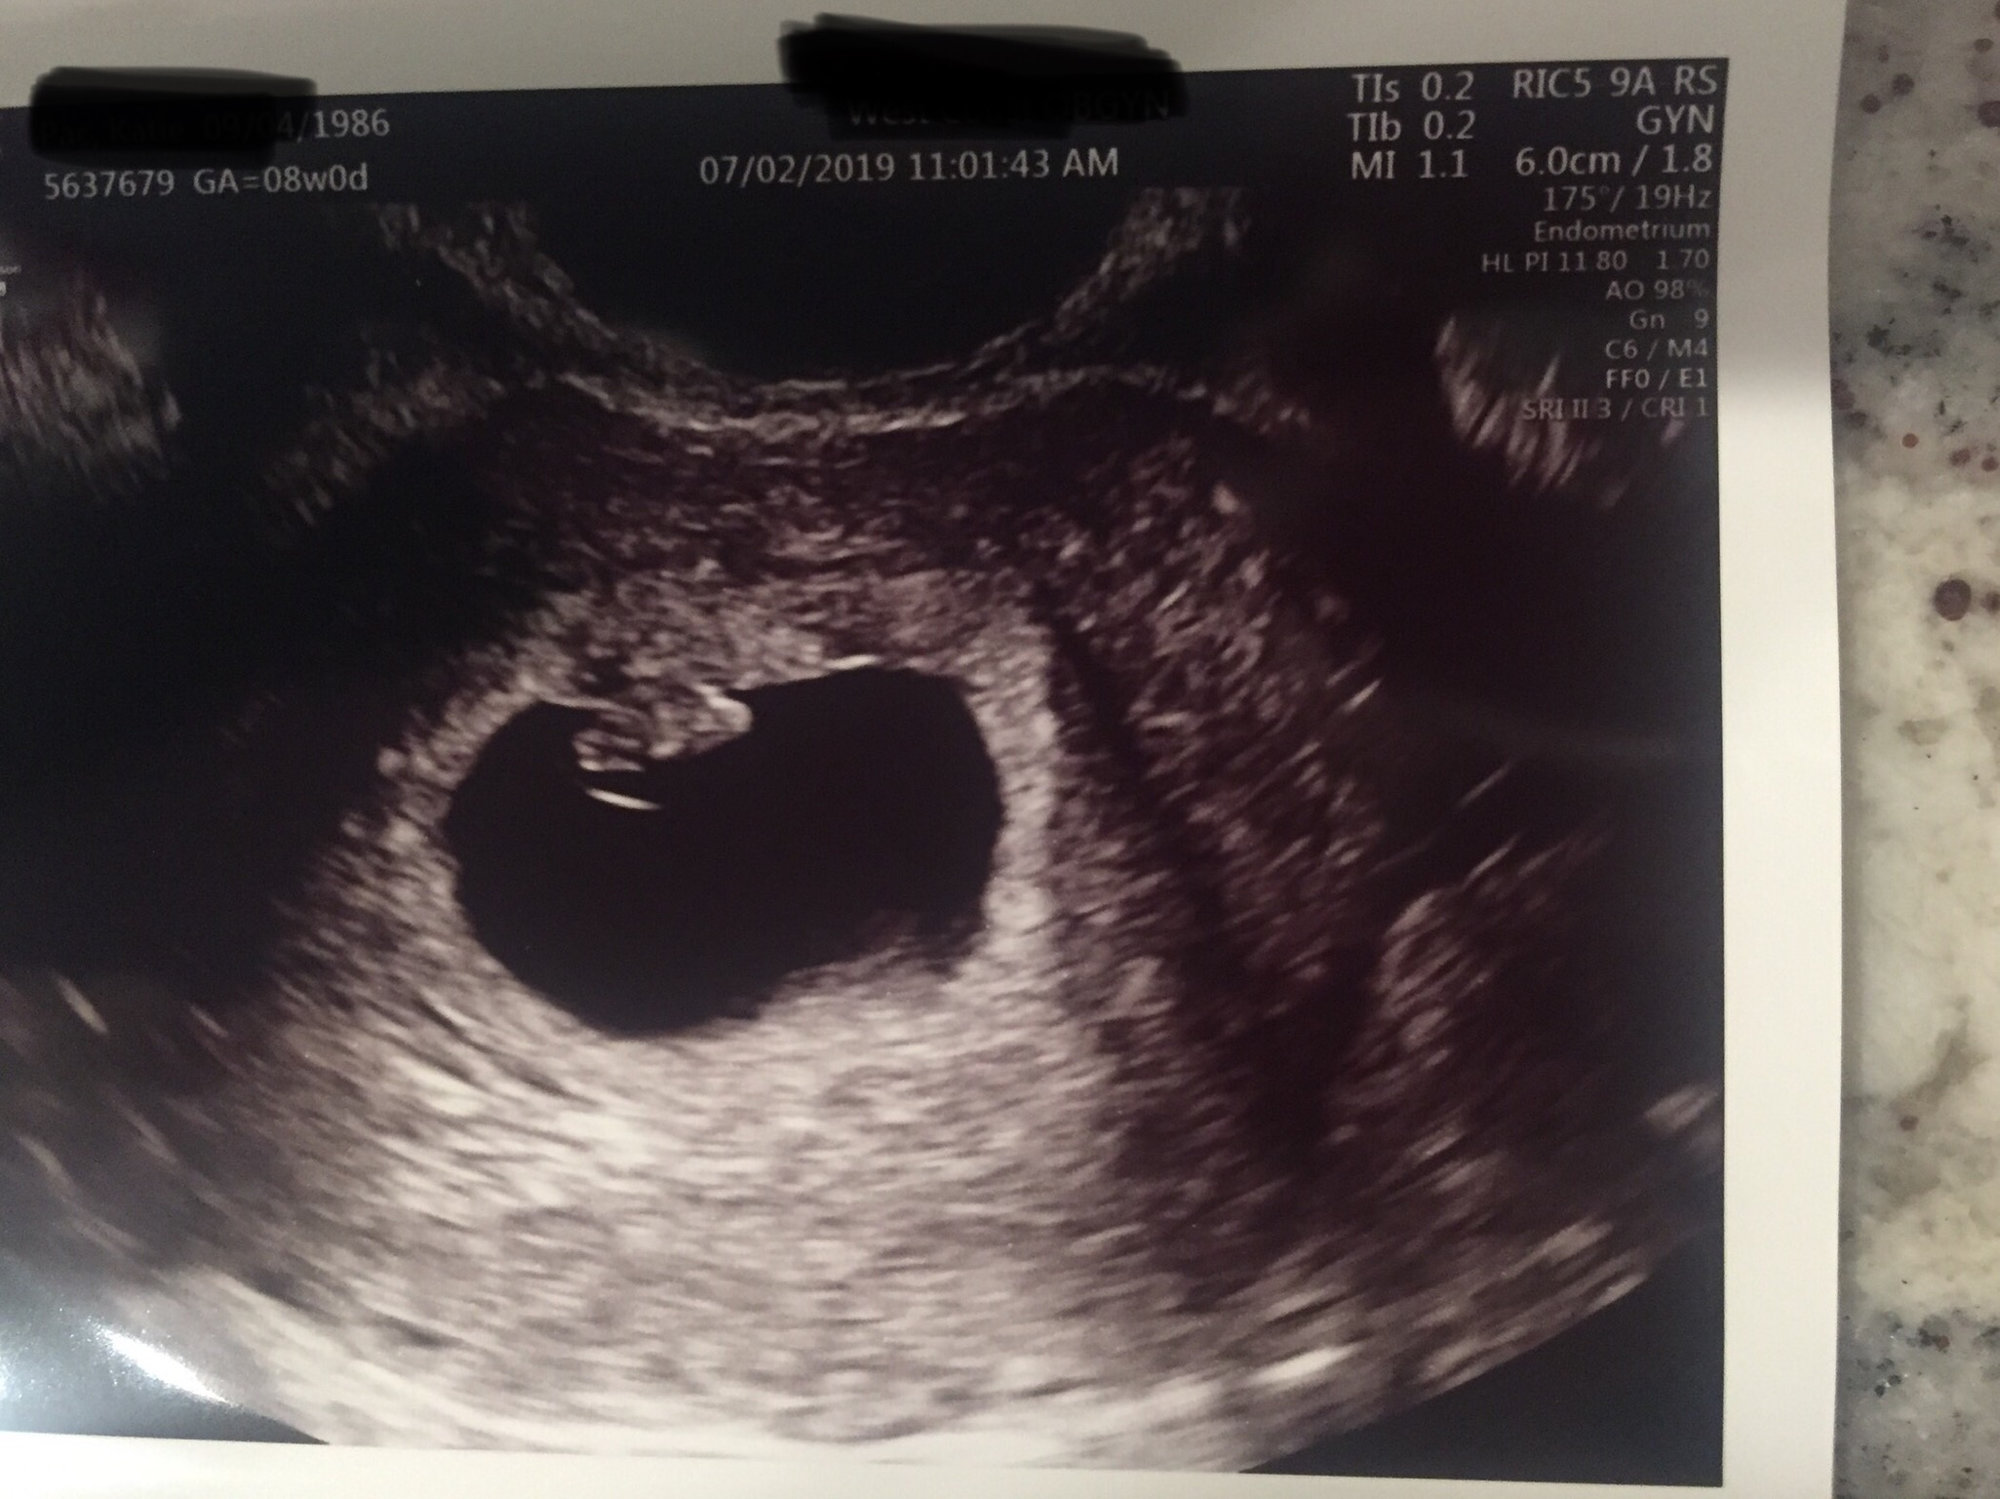

6 weeks, 4 days, and we saw his/her heartbeat!!!! 116 bpm, which doc said is on the slow side, but normal for having a brand new heart. Already in love, and praying we welcome this baby in February